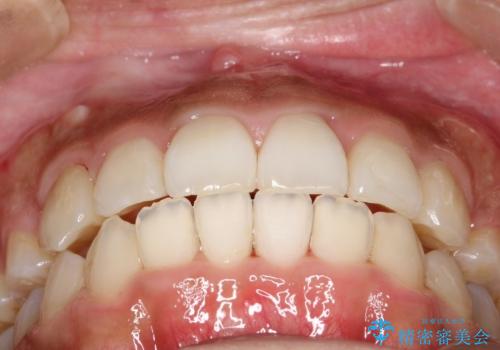

人生が変わる 困難を極める咬合状態に歯列矯正単独で挑戦する

骨格的要因を背景にもつ不正咬合のため、歯列矯正単独での改善は困難と判断しましたが、患者さんとの相談の結果、歯列矯正単独で可能なところまで一緒に頑張りましょうということで、治療をすすめました。

シビアな叢生や開咬も改善することができ、想像以上の改善に時間をかけた甲斐があったと満足していただけました。